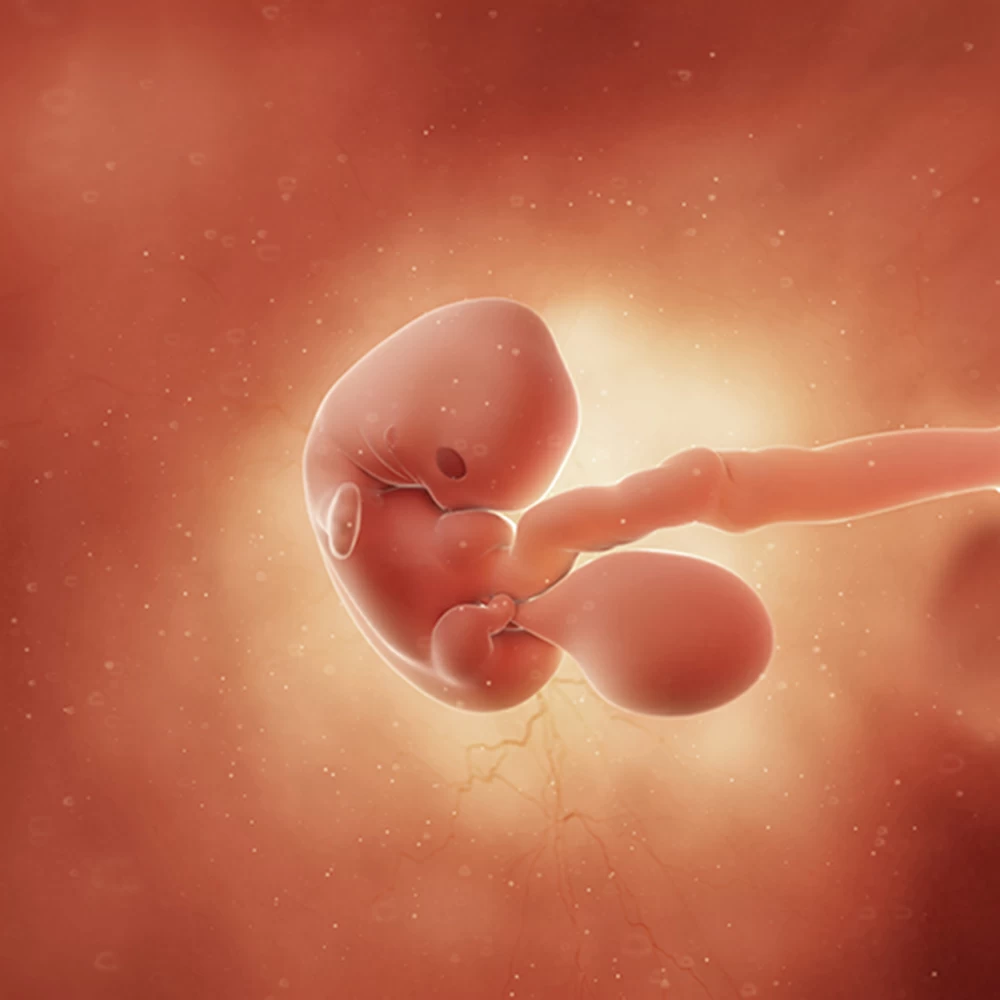

Дневник беременности